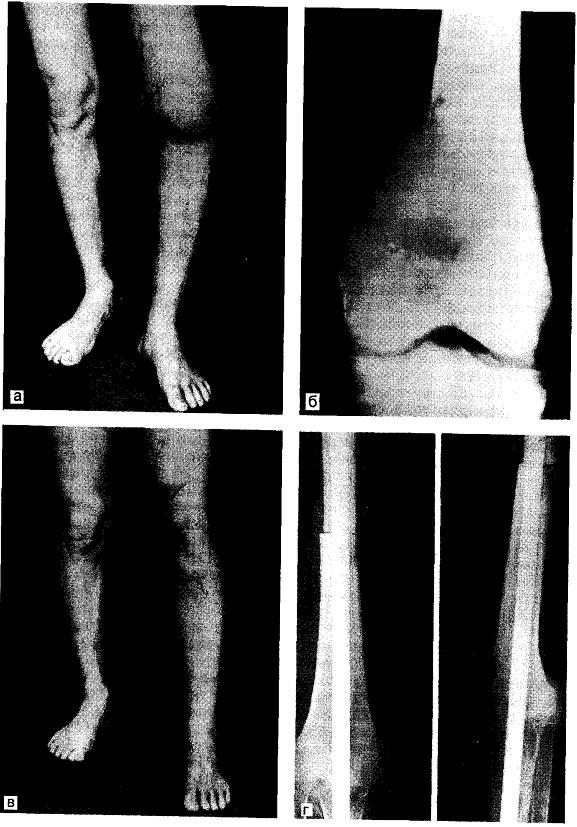

Злокачественная фиброзная гистиоцитома кости - относительно редкая (около 2% первичных злокачественных опухолей скелета) злокачественная опухоль с резко выраженным полиморфизмом веретеноклеточных элементов, лишённая каких-либо признаков гистологической дифференцировки. Встречается в молодом и старческом возрасте (средний возраст 50 лет), несколько чаще у мужчин. Локализуется в основном в метафизах длинных костей - бедренная кость, кости голени, плечевая кость, реже в краниофациальных костях, крайне редко в костях позвоночника и рёбрах.

Боль, болезненность при пальпации, часто патологические переломы.

Рентгенологически - остеолитический эксцентрично расположенный очаг без признаков обызвествления и чётких границ; периостальная реакция обнаруживается редко; обычно разрушение кортикальной пластинки и распространение опухоли в мягкие ткани.